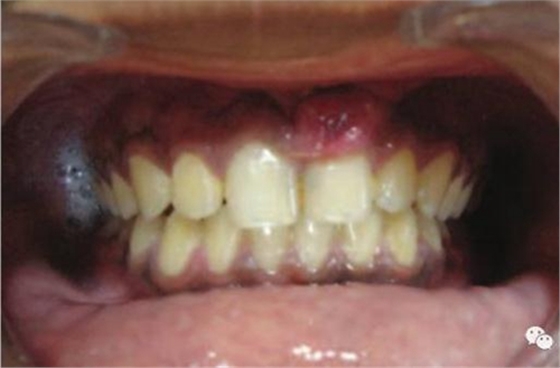

激光治療后即刻

治療前和2個(gè)月后效果對比